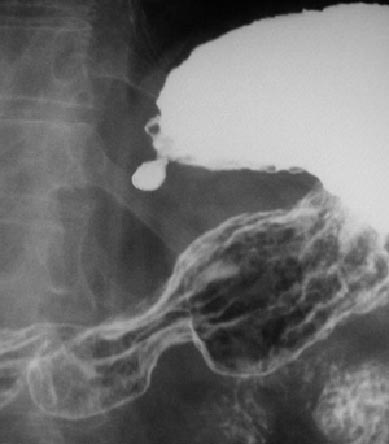

SIGNO DE LA LÍNEA DE HAMPTON

Signo de úlcera péptica en el estudio baritado. Vista la úlcera de perfil, la línea de Hampton es una fina línea (1 mm aproximadamente) muy bien delimitada, que atraviesa la base del nicho. Representa la mucosa gástrica colgante en los bordes de la úlcera benigna. En este caso los márgenes de la úlcera no presentan el edema que constituye el Signo del halo o collar ulceroso.